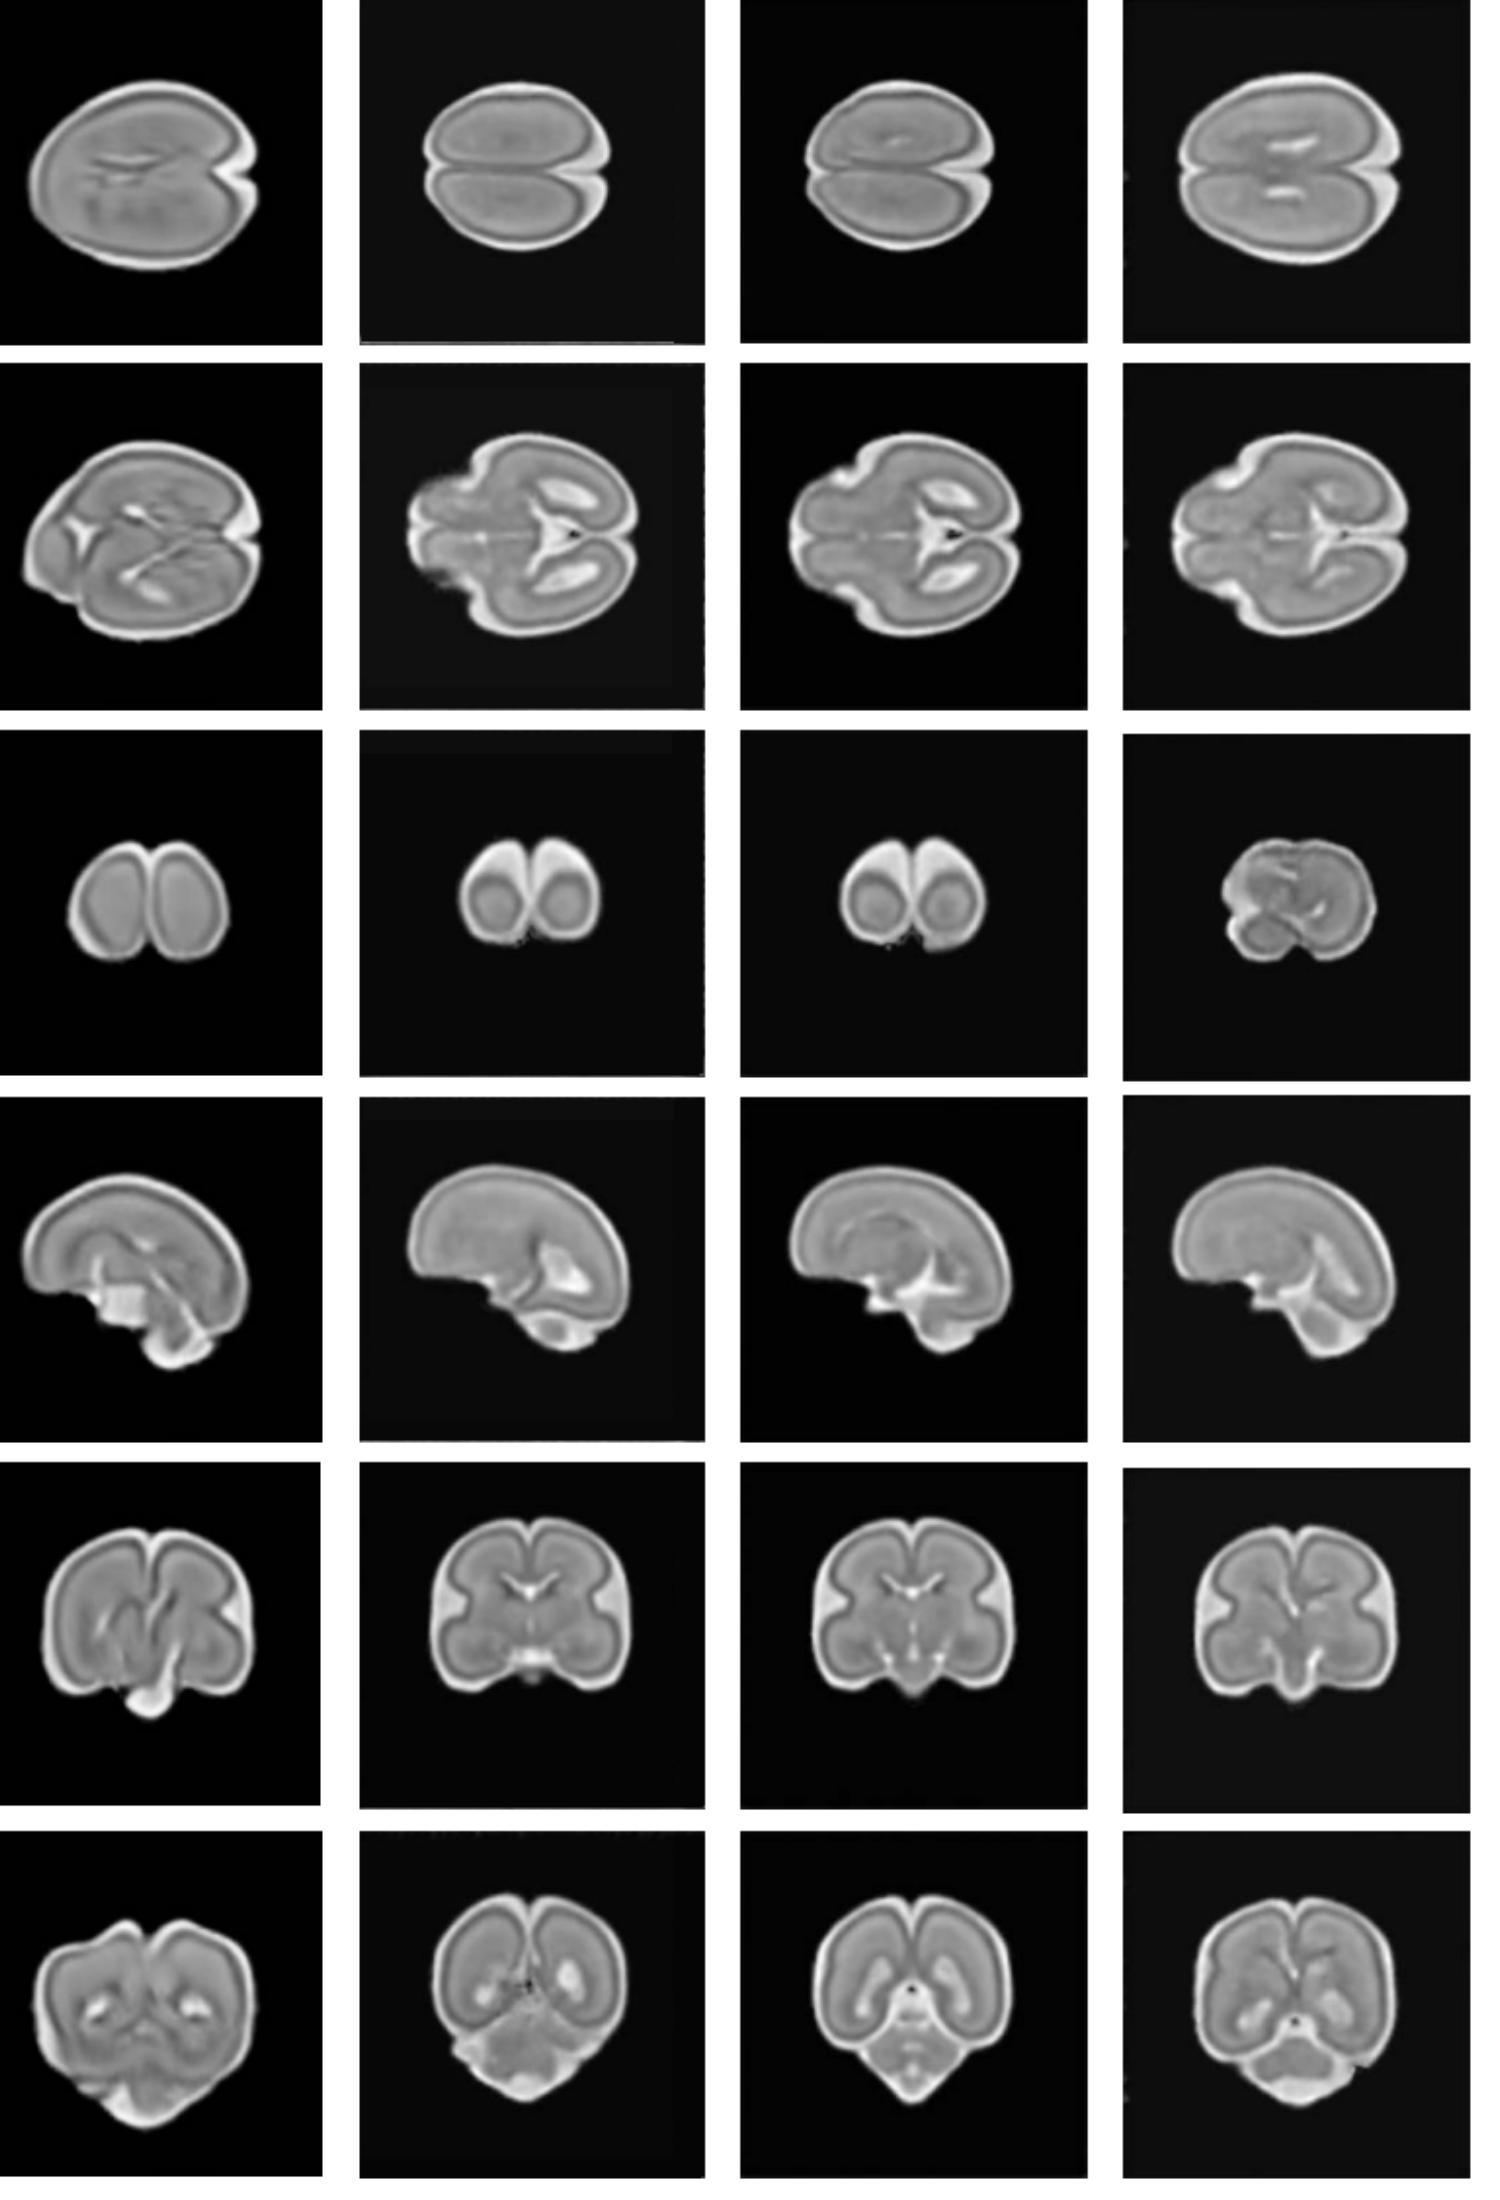

Working with Dr Lorenzo Venturini (DPhil 2022), Professors Namburete, Noble and Papageorghiou also co-authored a paper exploring the use of convolutional neural networks, or CNNs, for the segmentation of multiple fetal brain structures in 3D ultrasound images.

The proof-of-concept paper looked at whether the researchers could apply a machine-learning based method for automated segmentation of multiple fetal brain structures. This sort of accurate detection can track brain development through gestation, helping predict fetal health outcomes.

Titled BEAN (Brain Extraction and Alignment Network), the collaborative paper presents a multi-stage CNN that allows for the actual shape of the brain to be analysed, which is fundamental to tracking how the brain matures.

The INTERGROWTH-21st (International Fetal and Newborn Growth) Consortium, which is dedicated to improving perinatal health, also looked at creating standards for five fetal brain structures.

Fetal brain anatomy is assessed routinely as part of the 20-week anomaly scan. The measurements are assessed against one of several reference charts. However, these have limitations, and there can also be a lack of consistency in the interpretation of ultrasound images of the fetal central nervous system.

Using a study population consisting of women at low risk of adverse pregnancy and perinatal outcomes, the researchers produced international size standards for fetal brain ultrasound measurements.

Alongside developing standards for fetal brain structures, researchers in the INTERGROWTH-21st project, which involved nearly 60,000 mothers and babies in eight urban areas in Brazil, China, India, Italy, Kenya, Omen, the UK and the USA, were also able to develop international standards for fetal cerebellar growth and Sylvian fissure maturation.